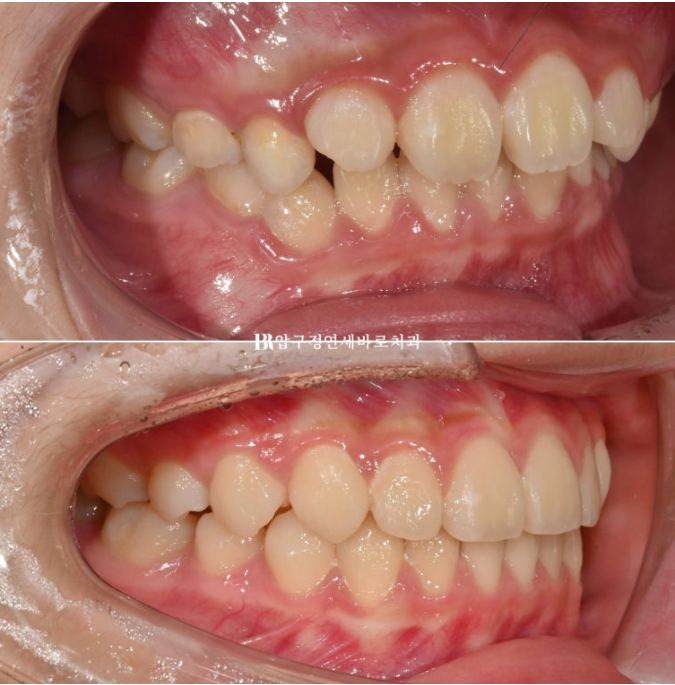

그 이후 3개월 간격으로 정기검진을 하던 중 송곳니가 나오기 시작했는데 송곳니 날 공간이 약간 좁은 것이 관찰되었습니다.

송곳니가 충분히 나오면 재제작을 하기로 하고 의도적으로 더 기다려서 7개월 후인 24년 1월 재제작을 시작했습니다.

24.01

아래는 유지가 잘 되어서 문제가 없었으니 위 송곳니 날 자리가 부족해서 덧니처럼 회전이 된 채 내려오는 것이 보입니다.

이런 부분 때문에 인비절라인 퍼스트는 18개월의 보증기한을 두고 있습니다.

예상과 벗어난 부분을 고치기 위해서입니다.

보증기간 내에 발견된 문제점은 얼마든지 해결이 가능합니다.

재제작에 들어갔고 24년 7월까지, 6개월간 한 세트의 추가장치를 더 꼈습니다.

마지막 장치를 낀 후 모습입니다.

24.07

덧니처럼 나와있던 송곳니는 잘 배열이 되었고 그 사이 마지막 유치 어금니 4개가 빠지고 영구치 작은 어금니가 내려오는 중입니다.